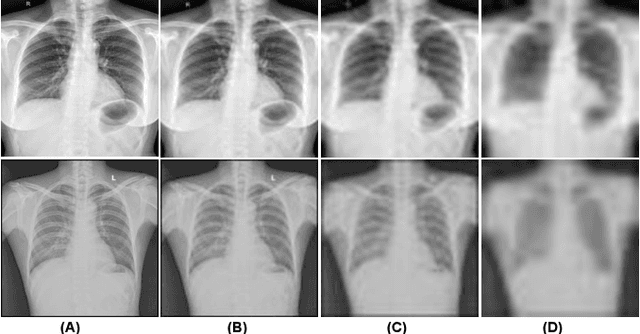

Abstract:This research addresses the challenges of diagnosing chest X-rays (CXRs) at low resolutions, a common limitation in resource-constrained healthcare settings. High-resolution CXR imaging is crucial for identifying small but critical anomalies, such as nodules or opacities. However, when images are downsized for processing in Computer-Aided Diagnosis (CAD) systems, vital spatial details and receptive fields are lost, hampering diagnosis accuracy. To address this, this paper presents the Multilevel Collaborative Attention Knowledge (MLCAK) method. This approach leverages the self-attention mechanism of Vision Transformers (ViT) to transfer critical diagnostic knowledge from high-resolution images to enhance the diagnostic efficacy of low-resolution CXRs. MLCAK incorporates local pathological findings to boost model explainability, enabling more accurate global predictions in a multi-task framework tailored for low-resolution CXR analysis. Our research, utilizing the Vindr CXR dataset, shows a considerable enhancement in the ability to diagnose diseases from low-resolution images (e.g. 28 x 28), suggesting a critical transition from the traditional reliance on high-resolution imaging (e.g. 224 x 224).